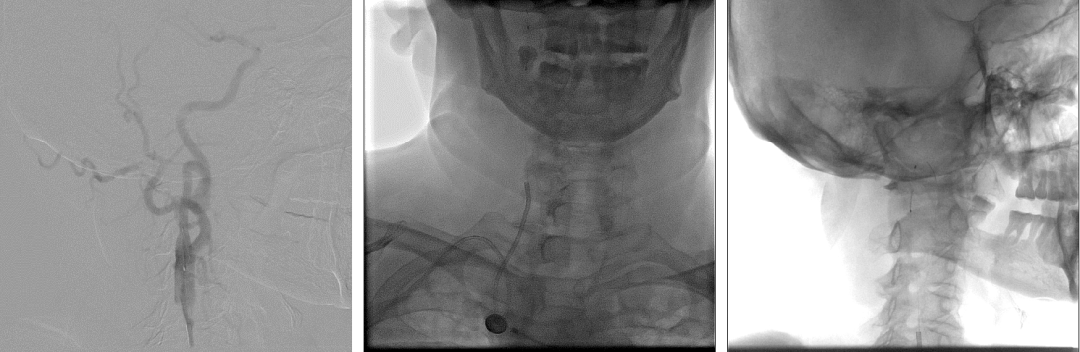

头颅核磁提示:右侧大脑半球、双侧小脑半球多发散在DWI高信号,考虑急性亚急性脑梗死;头颅MRA未发现明显重度狭窄及闭塞大血管。

急诊头颅MRA未见颅内大血管较重狭窄或闭塞。

DSA:经股动脉行主动脉弓造影显示:二型弓,头臂干可见充盈缺损,头臂干分叉处迂曲。